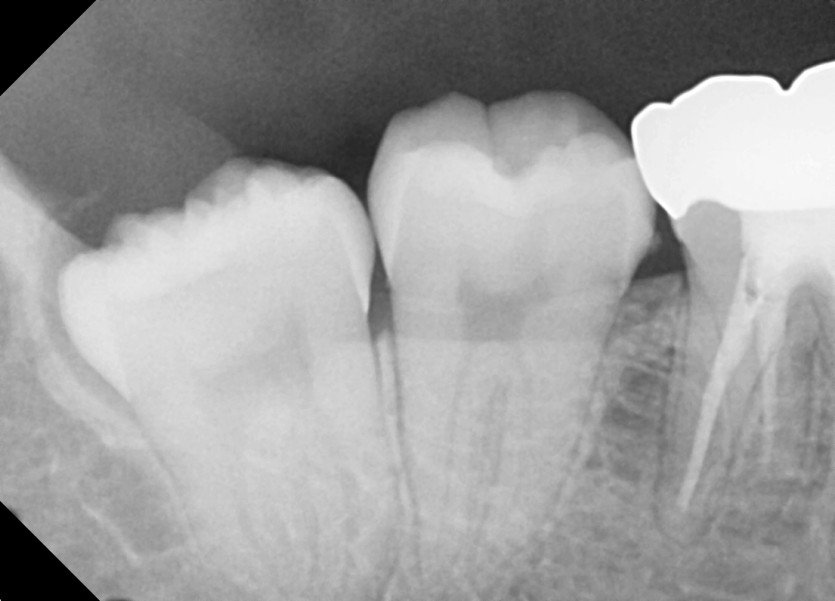

#48 사랑니 발치

구강외과 전문의가 당일 발치했습니다.